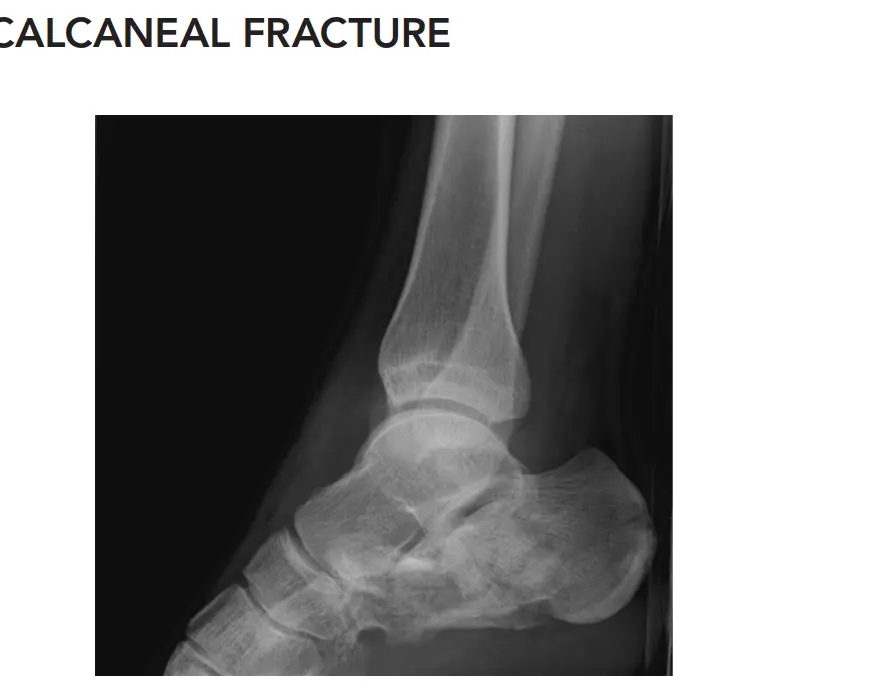

التصوير بالأشعة السينية (X-rays)

تُعد الأشعة السينية هي الخطوة الأولى في التصوير، حيث توفر صورًا سريعة للعظام:

المنظر الجانبي (Lateral View):

يظهر هذا المنظر التغيرات في زوايا مهمة مثل:

- زاوية بوهلر (Bohler's Angle): تُقاس هذه الزاوية بين خطين على الأشعة السينية الجانبية. في الكسر المعقد، تنخفض هذه الزاوية بشكل كبير (الطبيعي 20-40 درجة). في الحالة المذكورة، انخفضت إلى 5 درجات فقط، مما يشير إلى انهيار كبير في ارتفاع الكعب.

- زاوية جيسان (Gissane's Angle): تُعرف أيضًا بالزاوية الحاسمة، وتزداد في كسور الكعب (الطبيعي 100-120 درجة). في حالتنا، ارتفعت إلى 140 درجة، مما يدل على تضرر المفصل تحت الكاحل.

- يُظهر المنظر الجانبي أيضًا نمط الكسر، مثل "اللسان" (Tongue-type) أو "انضغاط المفصل" (Joint Depression-type).

- المنظر المحوري (Axial View - Harris View): يكشف هذا المنظر عن اتساع عظم الكعب وتشوهه، بالإضافة إلى تفتت الجدار الجانبي.

- المنظر الأمامي الخلفي للكاحل (AP Ankle View): يستخدم لاستبعاد كسور الكاحل أو عظم الظنبوب.